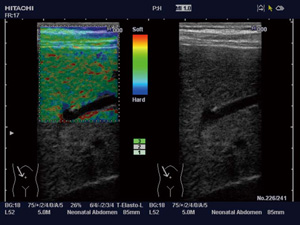

2.Real-time Tissue Elastography(Elastography)

超音波検査で組織の硬さを画像化する,世界初の技術である。力を加えたときに,柔らかいものであれば大きな変形を生じるが,硬いものであればほとんど変形しないという特性を応用し,その変形の程度を色で表している。

目的部位に探触子を軽く圧迫させるだけの簡単な走査で行える。生体内の組織歪みから相対的な硬さを高速演算し,硬さ(変形)の程度をリアルタイムにカラー表示することにより,周囲よりも硬い部分は青く表示される(図8)。

乳腺領域で始まったElastographyは,肝臓などの腹部領域を対象とした研究へと広がっており,その有用性が期待されている。 |

図8 Elastography(正常肝) |

3.Strain Ratio

Elastography画像において,任意の2か所の比を数値で表示ことができる。例えば,乳腺領域では脂肪組織と関心領域の比(Fat Lesion Ratio:FLR)を求めることができ,組織性状の研究などへの応用が期待されている(図9)。 |

図9 FLR(乳腺) |